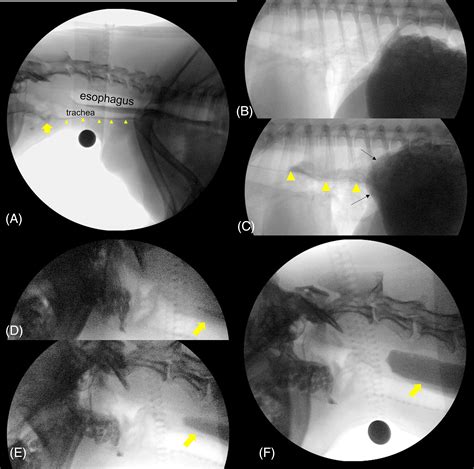

The Videofluoroscopic Swallow Study (VFSS), also known as a modified barium swallow, is a diagnostic procedure that uses fluoroscopy and a barium-based contrast material to visualize the swallowing process. This study helps identify the specific phase of swallowing that is impaired, whether it is the oral, pharyngeal, or esophageal phase.

During the study, the patient will be asked to swallow various consistencies of barium-coated food and liquids while being observed under fluoroscopy. This real-time imaging allows the healthcare team to assess the swallowing mechanism in detail.

1. The patient is positioned in front of a fluoroscopy machine, which emits X-rays to create real-time images of the swallowing process.

2. The patient is given barium-coated food and liquids of different consistencies, such as thin liquids, thick liquids, pudding, and crackers.

3. The healthcare team observes the patient’s swallowing mechanism, noting any abnormalities or difficulties.

The results of a Videofluoroscopic Swallow Study provide valuable information about the swallowing process. The healthcare team looks for various indicators, including:

• Aspiration: The entry of food or liquid into the airway, which can lead to pneumonia.

• Penetration: The entry of food or liquid into the laryngeal vestibule but not below the vocal folds.

• Residue: The remaining food or liquid in the mouth, pharynx, or esophagus after swallowing.

• Delay in swallow initiation: A delay in the start of the swallowing reflex.

• Reduced tongue base retraction: Inadequate movement of the tongue base, which can affect the clearance of food from the mouth.

• Detailed Visualization: Provides a clear view of the swallowing process, allowing for precise identification of abnormalities.

• Real-Time Assessment: Enables real-time observation of swallowing, which is crucial for diagnosing dynamic issues.

• Comprehensive Evaluation: Assesses all phases of swallowing, from the oral phase to the esophageal phase.